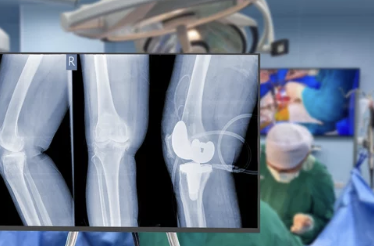

| MRI 검사 | 연골 손상, 인대 파열, 관절 내 염증 확인 |

- 무릎 관절염과 연골 손상 여부를 구별하기 위해 MRI 검사가 효과적입니다.